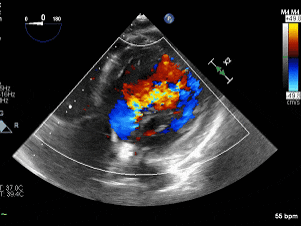

术前主动脉瓣反流

(深胃底五腔心切面)

1.主动脉瓣二叶式畸形(Type 1型):主动脉瓣重度关闭不全,主动脉根部及升主动脉增宽;2.左心增大,左室整体收缩功能正常范围;3.三尖瓣少量反流。